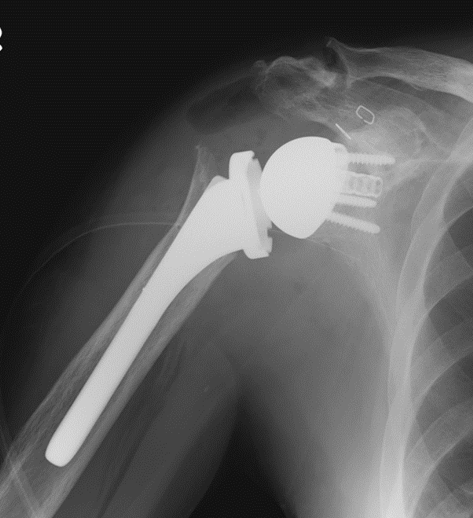

腱板断裂を放置すると、上腕骨頭が上方に移動し、上腕骨と肩甲骨の適合性が悪くなり、関節が傷んできます。そうなると、肩関節の痛みや肩が挙がらない症状が出現します。腱板断裂後に関節症性変化を生じ、肩関節の挙上が困難な65歳以上の患者さんには、リバース型人工肩関節置換術を行っております。この手術により肩関節の痛みが軽減し、肩関節の挙上を改善することが期待できます。

変形性肩関節症

肩関節の軟骨が変性すると、肩関節の痛みや挙げにくい症状が出現します。鎮痛薬や関節内注射などの保存治療を行っても症状が改善しない患者さんに対して、人工肩関節全置換術を行っております。人工肩関節全置換術は除痛効果に優れ、また肩関節の動き(可動域)が改善することが期待されます。